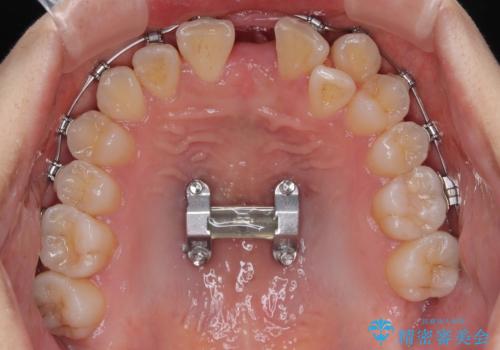

MARPEについて

MARPE(Mini screw assisted rapid palatal expansion )は、上顎の幅を広げる矯正治療です。

歯だけでなく、あごの骨に直接力をかけて広げるのが特徴です。

これまで難しかった大人の方でも、上あごの拡大が可能な場合があります。

上顎の骨に小さなネジ(マイクロインプラント)を使用し、装置をしっかり固定します。

その力で上あごの正中(真ん中の骨のつなぎ目)を少しずつ広げていきます。